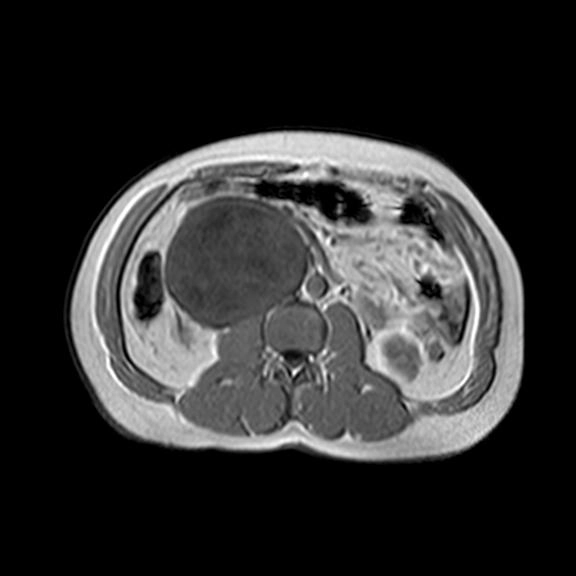

Khối u vỏ bao thần kinh ngoại biên ác tính (Malignant Peripheral Nerve Sheath Tumor - MPNST)